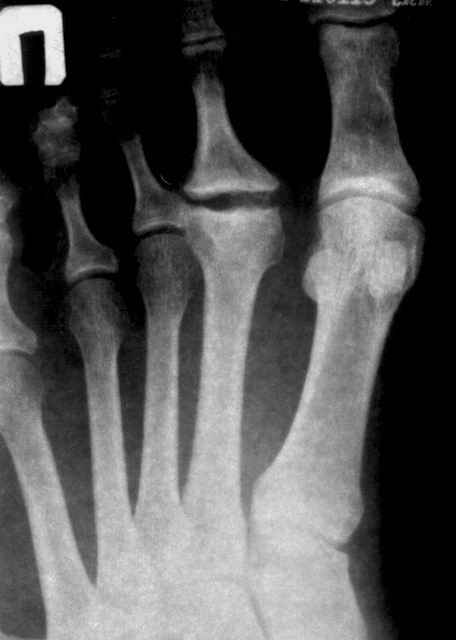

У меня была похожая пациентка - тоже с вальгусной деформацией, неуточненная травма 3 года назад. Обратилась по поводу болей в области головки 2 плюсневой кости, в течение 2-х месяцев. При осмотре - небольшая припухлость, движения в суставе в полном объеме, даже некоторая "разболтанность" отмечается. Боли усиливались в основном при ходьбе на каблуке, когда увеличивалась нагрузка на головку плюсневой кости. У неё были более выраженные изменения на Rg-грамме (во вложении), а здесь - только если в прямой проекции (справа) можно заподозрить некоторую уплощенность головки...

Боли прошли после курса Цель Т, внутрисуставно и вокруг. Rg-грамма осталась прежней. Уже 3 месяца не появляется.